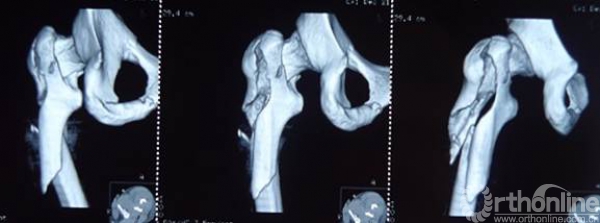

进针点和力线很难把握,即使应用很巧妙的复位技术获得了术后很好的力线,避免了髋内翻,但如此大块的骨块劈裂游离不处理,会存在退钉和骨不连或者髓内钉断裂的风险。

钱XX,女,43岁

术后